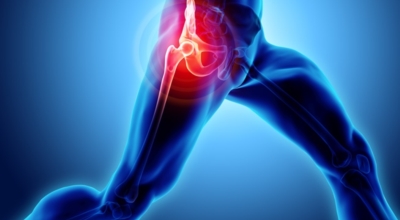

고관절이란 골반을 지탱하는 관절로서 근육과 힘줄로 구성되어 있습니다. 학계에서는 고관절을 엉덩이 관절이라고 부르기도 하며 인체의 하중을 지탱하는 아주 주요한 관절입니다. 각별히 고관절은 우리가 정상적으로 서있거나 움직일 수 있게 만들어주고 달리기, 점프, 무거운 무게를 들 때 최대 체중의 2~10배 가량의 하중을 받기 때문에 적절한 관리가 필요해요. 오늘은 고관절에서 생기게 될 수 있는 고관절 통증 증상에 대하여 알려드릴게요.

고관절 통증 증상

고관절염은 고관절에 나타나는 관절염을 말하며 고관절의 연골이 닳게 되면서 뼈와 뼈가 서로 부딪히며 통증을 일으키게 됩니다. 고관절염 초기 증상으로는 사타구니 부위가 불편하게 느껴지며, 무리하면 통증이 생길 수 있다고 하며, 관절염 증상이 심해지면서 사타구니에서 느끼던 통증이 허벅지와 엉덩이 통증으로 이어지기도 하는데, 고관절염 통증 증상으로 초기에는 허리 통증이 나타나 허리 질환과 혼동하기 쉬우며 각별히 척추질환이 있는 사람은 고관절 통증 증상과 마찬가지로 엉덩이, 다리 통증이 동반되기 때문에 훨씬 헷갈리는 경우가 많다고 해요.